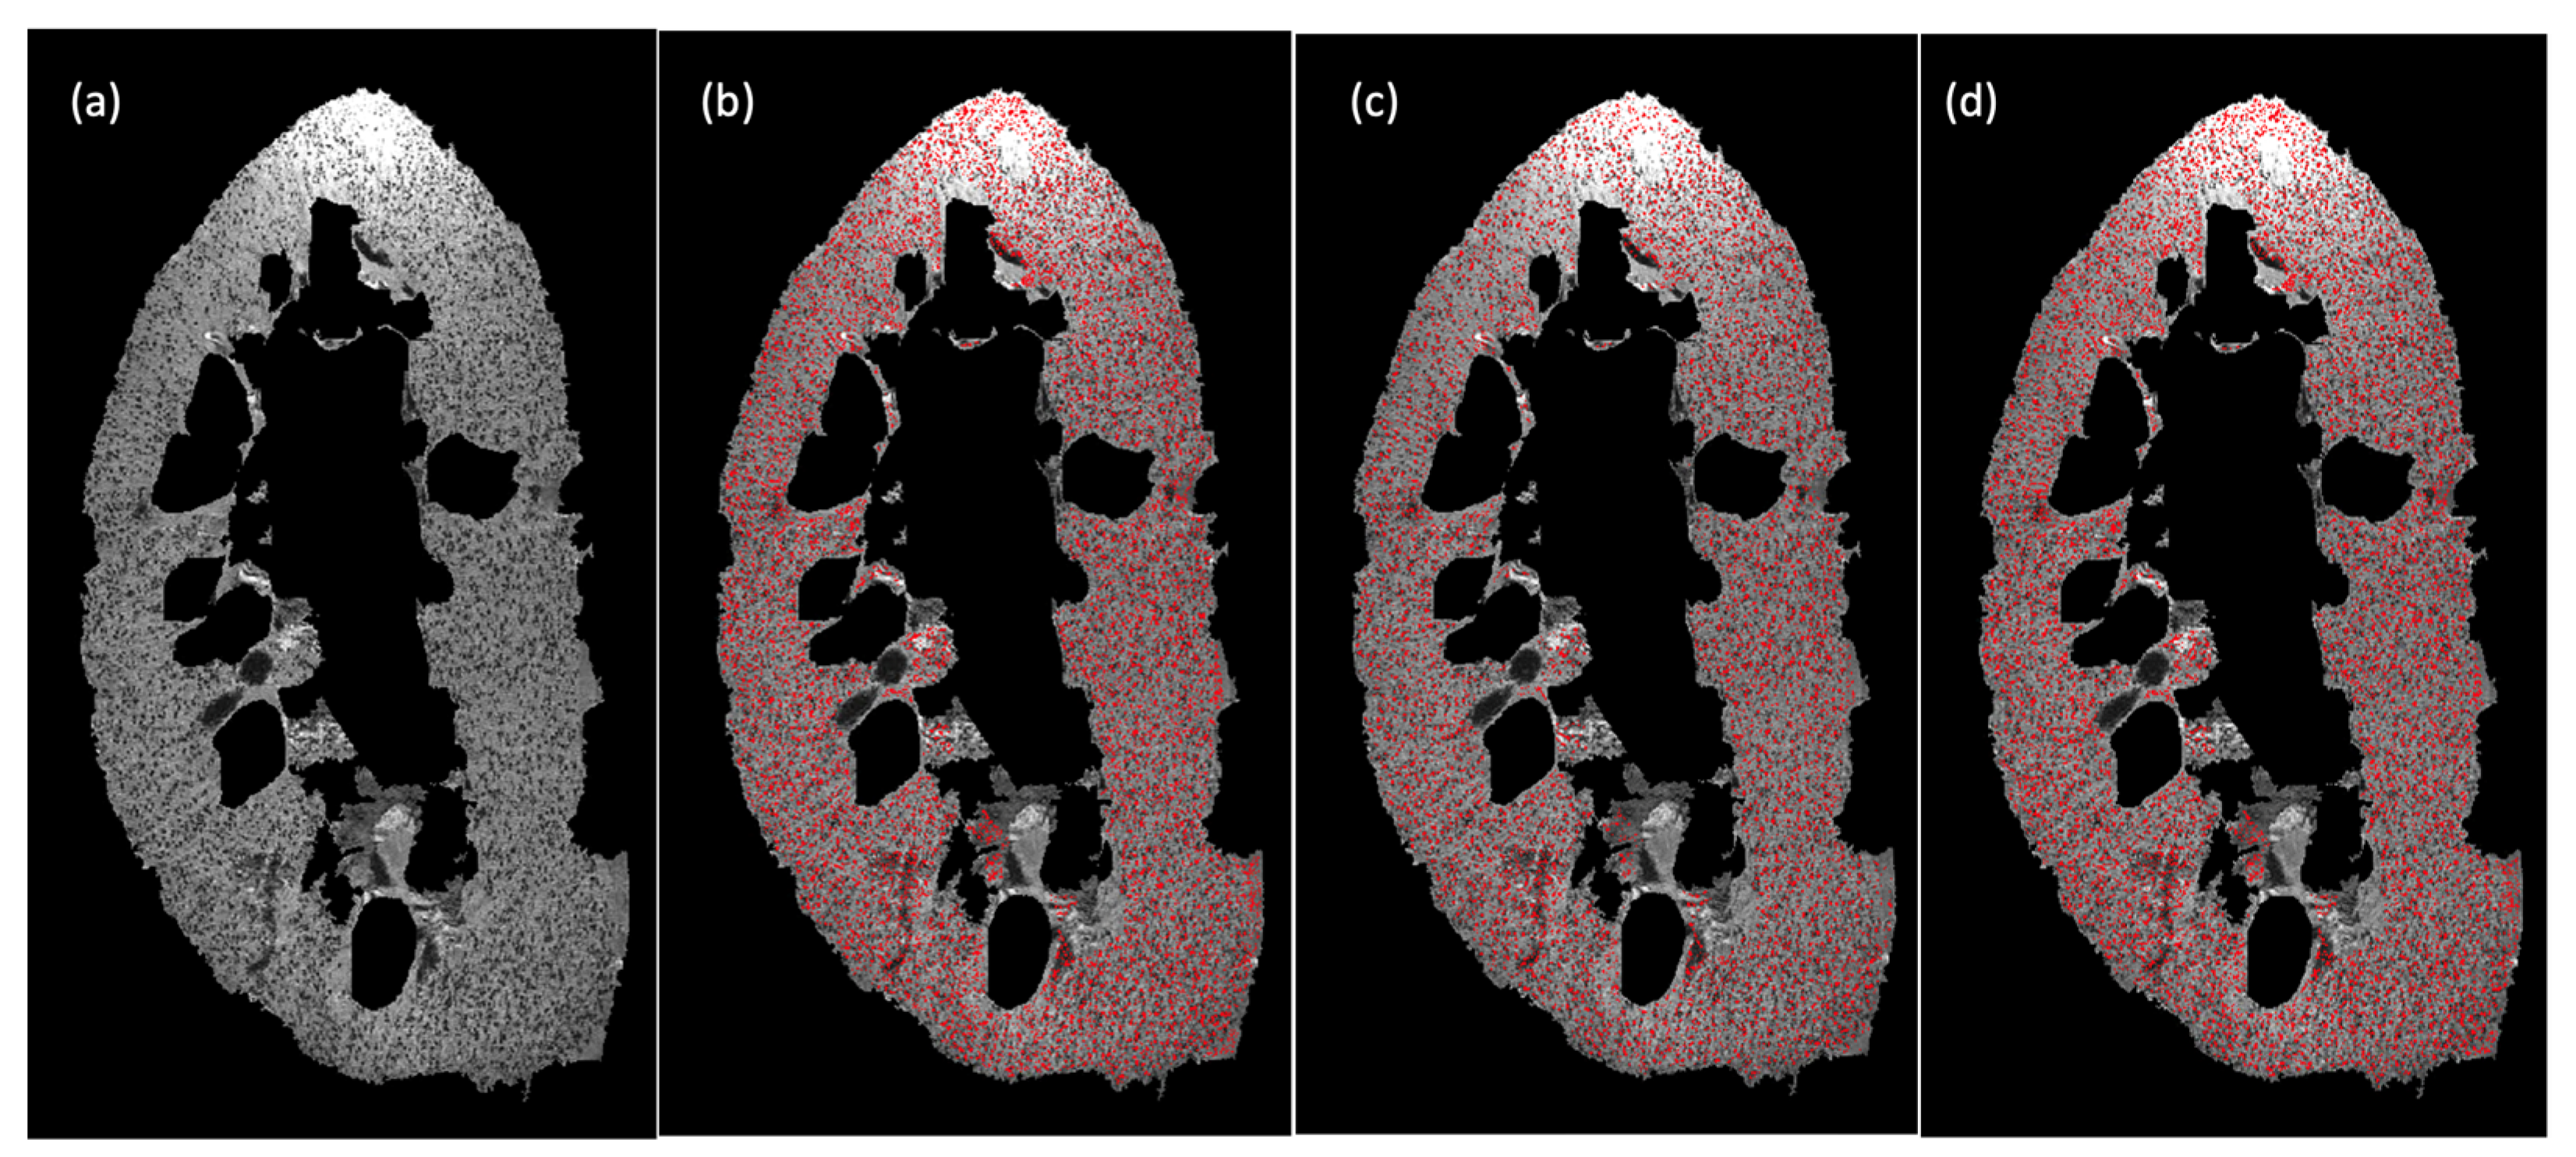

For illustration, example results from CF1 are shown in Figure 3. As seen, the BlobGAN trained on the FDD-Coreset has more similar glomerular segmentation results to the BlobGAN trained on the entire dataset than the BlobGAN trained on the IED-Coreset.

Figure 3.

Glomerular segmentation results from 3D MR images of human kidney (CF1 slice 256). (a) Original magnitude image. (b) Glomerular segmentation results of BlobGAN trained on entire dataset (1000 random samples). (c) Glomerular segmentation results of BlobGAN trained on IED-Coreset ( = 10). (d) Glomerular segmentation results of BlobGAN trained on FDD-Coreset ( = 10).